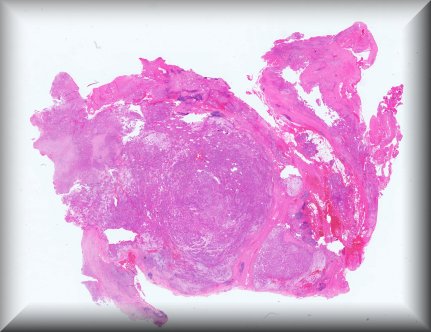

Fiona Roberts (Glasgow): 9 year old female with buphthalmos secondary to congential glaucoma. Protocol |